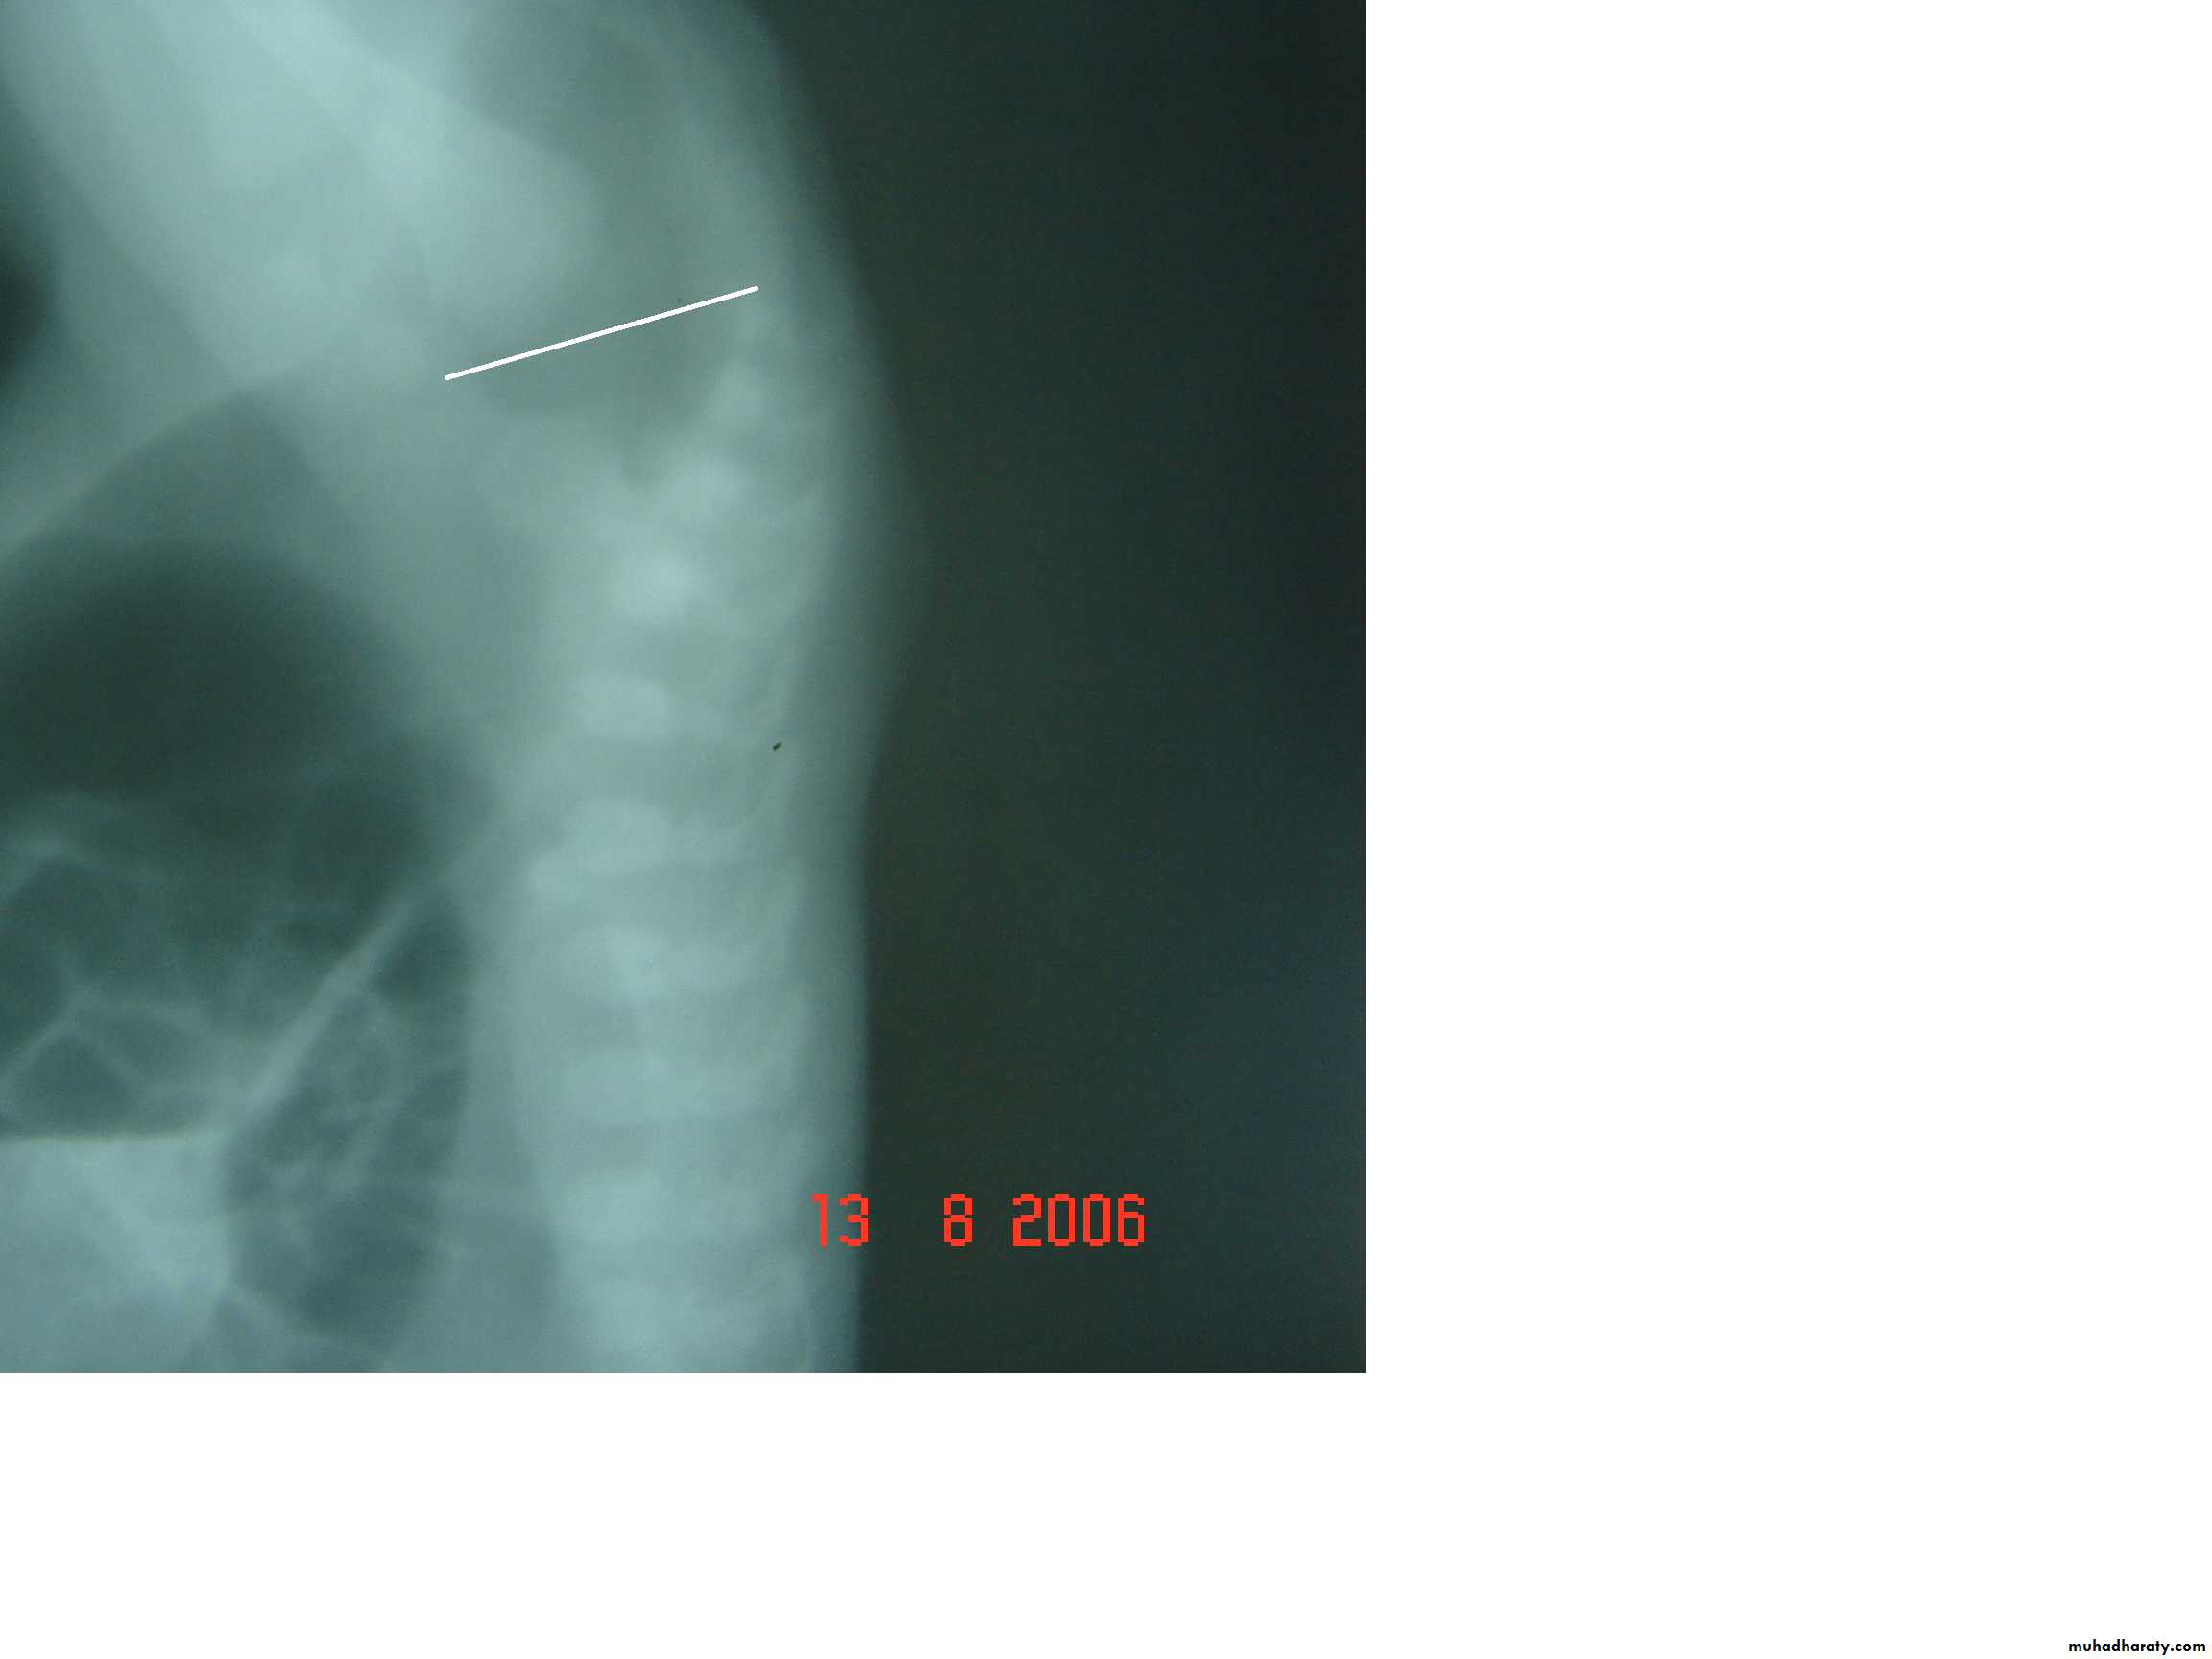

Radiology

Determined:

1-relation of rectum to sphincter muscle.

2-associated anomalies.

1-x-ray of the spine and chest (sacral , VATER).

2-Lateral invertogram ( pubococcegeal line) 18-24hr.after birth.

-gas shadow above this line suggest high type.

- gas shadow below suggest low type.

3-lateral decubitus X-ray.